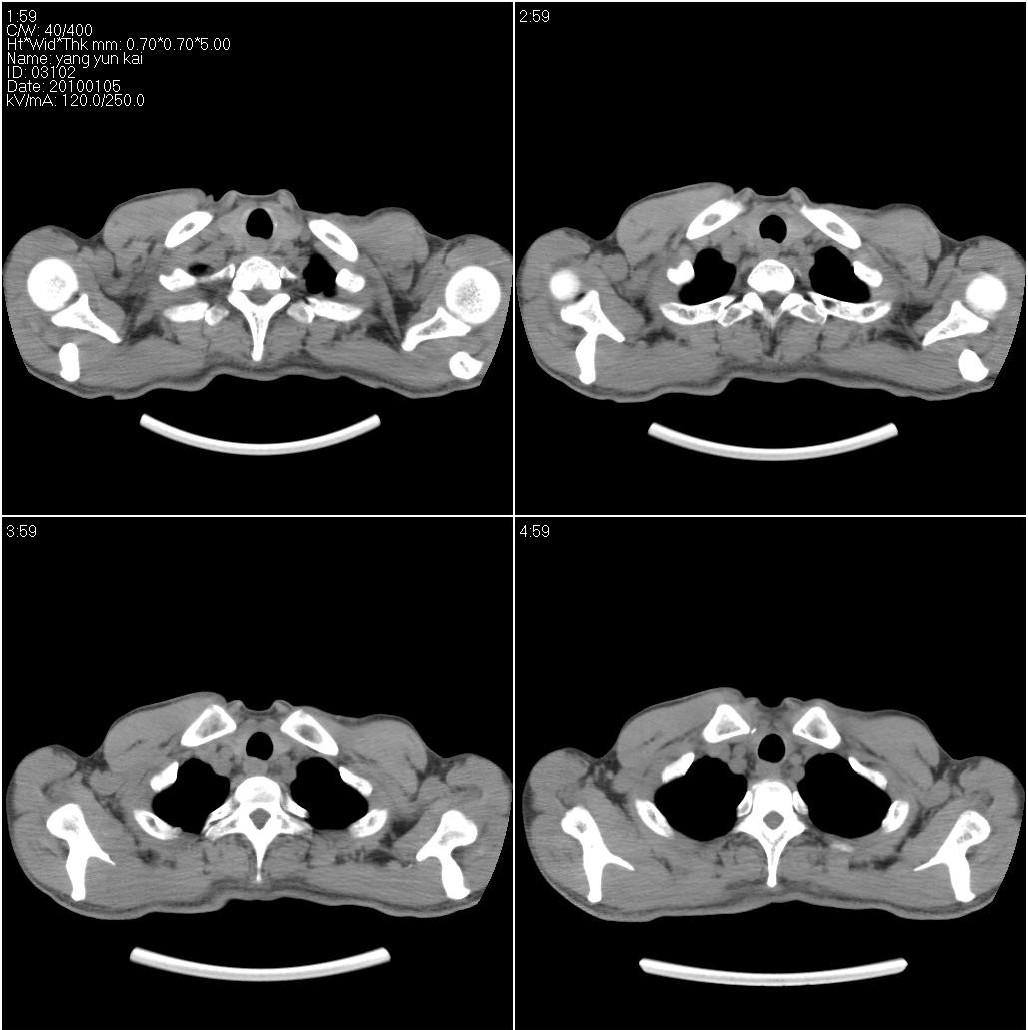

标题: CT23980:男性,47岁。近来咳痰、咳血,血沉增快(40左右),

男性,47岁。近来咳痰、咳血,血沉增快(40左右),痰中未检出结核杆菌。